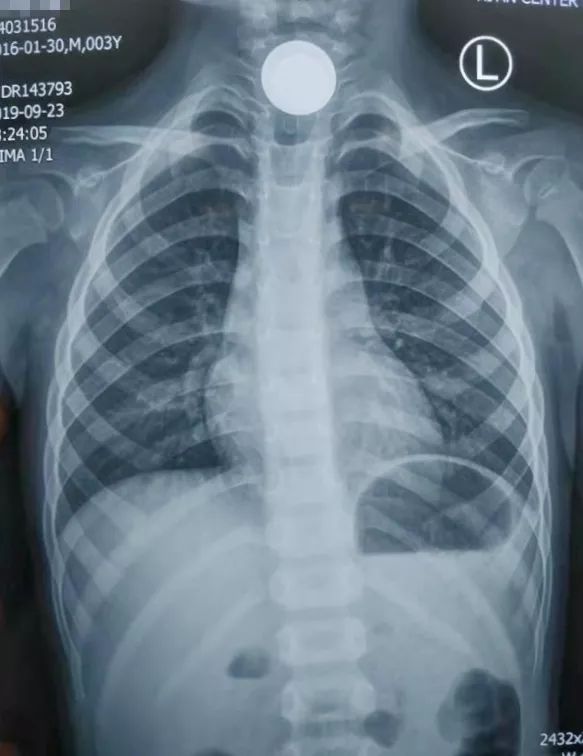

耳鼻喉科值班的主治医师王占江闻讯赶紧把孩子带进检查室,一问才知道,原来宝宝拿硬币玩,不小心将一枚一块钱硬币咽下去卡嗓子里了。孩子难受指着嗓子不停哭泣,痛苦的都说不清话了,家长心急如焚,经过详细的专科检查,王医生赶紧让孩子去拍了片子,出乎意料的是——宝宝食道里竟然卡顿了两枚硬币,一枚一元硬币一枚一角硬币!

通过急诊绿色通道,孩子顺利办好了入院手续,王医生给孩子完善急诊手术相关检查,联系手术室及麻醉科人员,禁食时间足够后安排急诊全麻手术。在手术医师、麻醉医师、手术护士紧张有序的配合下,终于将紧紧卡顿在孩子食道的一大一小两枚硬币顺利取出,孩子终于转危为安了,妈妈悬着的心也终于放下了。